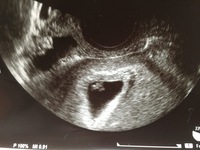

Aug 19, 17 · 妊娠6週目では、ママのお腹の中で赤ちゃんはどんどん成長していきます。ママ自体も胸の張りやつわりなど体の変化を感じる人もいます。また腹痛や出血などで赤ちゃんが大丈夫なのか不安になることも。今回は、コズレ会員のみなさんからお寄せいただいた妊娠6週目のエコー写真とそSep 27, 18 · 妊娠6週を過ぎると、胎嚢や心拍を確認できたり、耳や目・鼻や、心臓から延びる血管などが作られたりします。また、ママもつわりがひどくなったり、出血などに気をつける必要が出てきます。そこで、妊娠がわかったあとの過ごし方についてまとめました。Oct 04, · 現在妊娠6週4日です。 6週1日に病院で心拍確認済み。 エコーで子宮筋腫、子宮腺筋腫っぽいと言われています。 6週2日の夕方トイレに行くと、少量の赤い出血がありました。パンツに少し付着、トイレットペーパーで拭くと血と一緒に15mmほどの粒のようなものが付いていました。 出血

妊娠6週目 6w0d 6d のエコー写真とエピソード 妊娠2ヶ月 Cozre コズレ 子育てマガジン

妊娠6週3日 6w3d の超音波 エコー 写真

妊娠初期のエコー写真について質問です 妊娠6週目に病院で画像の真ん中の胎嚢 Yahoo 知恵袋